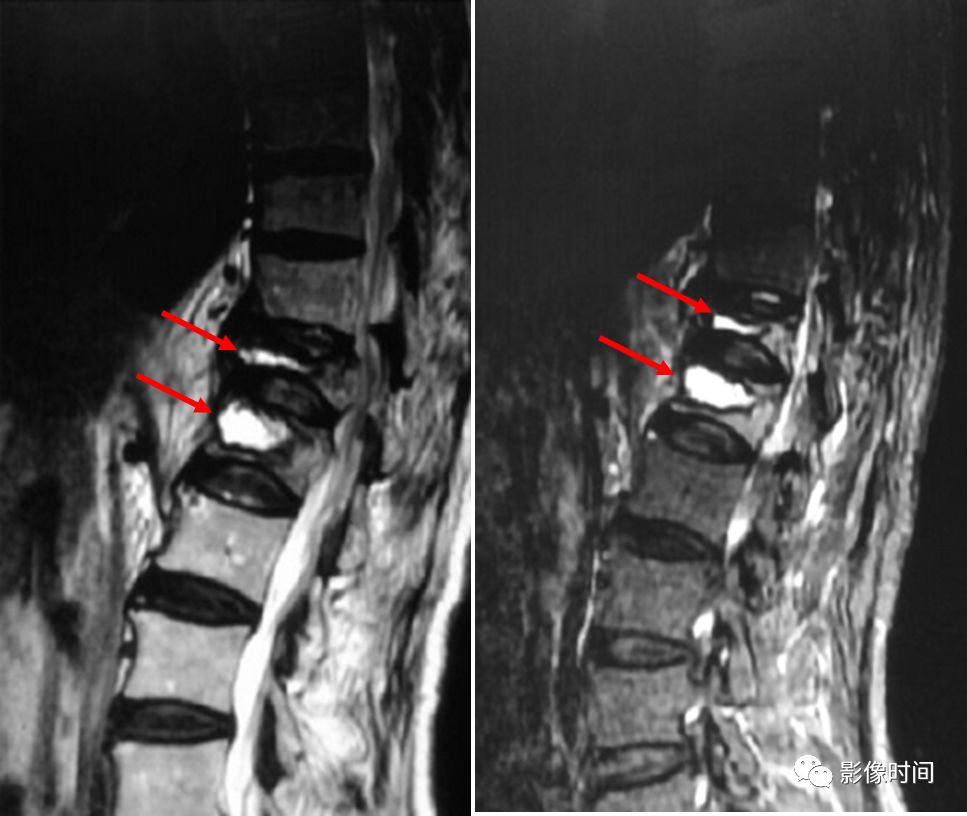

8牙膏征

牙膏征(Toothpaste sign)

牙膏征是指在矢状位脊柱影像中,脱出的椎间盘突入椎管内并向下游走,形似被挤出的牙膏而得名。

典型病例

矢状位 T2WI 像示脱出的椎间盘突入椎管,形似被挤出的牙膏,呈牙膏征(箭示)。